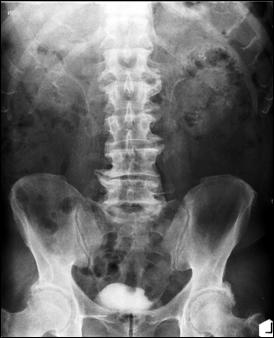

1. Diagnosticul diferential cu litiaza vezicala radiotransparenta

Figura 54. Imagine radiotransparenta (2,5/1,8 cm, vizibila pe cistografie) |